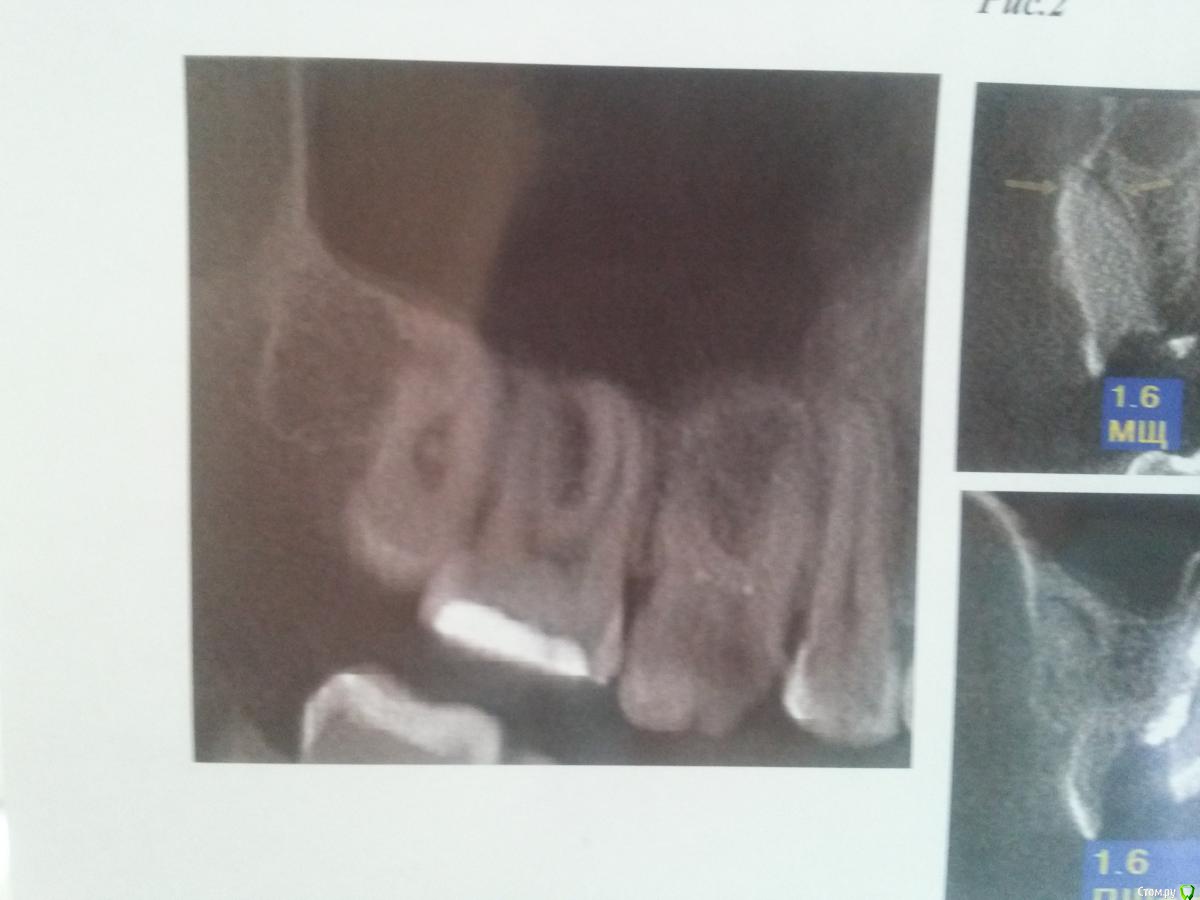

strator Опубликовано 4 мая, 2015 Автор Поделиться Опубликовано 4 мая, 2015 Это было в Москве или в другом городе? Сколько лет назад?дело было в Липецке лет 20 назад... Выкладываю описание и снимки проблемного зуба Ссылка на комментарий

strator Опубликовано 4 мая, 2015 Автор Поделиться Опубликовано 4 мая, 2015 продолжение снимков проблемного зуба Ссылка на комментарий

strator Опубликовано 13 мая, 2015 Автор Поделиться Опубликовано 13 мая, 2015 посмотрела описание своего КТ. указано, что у меня 4 канала, а судя по оплаченному мною счету лечили мне только 3 канала.подскажите, пожалуйста, сейчас хожу с лекарством получается в 3 каналах и временной пломбой. надо ли бежать к врачу и говорить еще об одном канале, либо до следующего посещения врача о забытом канале пока не думать? бывает ли такое, что врач не находит каналы? если все же у меня их 4, как в описании КТ, то по правильному врач заново должен все обработать и опять ходить с лекарством, либо он может уже начать полностью пломбировать все постоянно? спасибо. Ссылка на комментарий